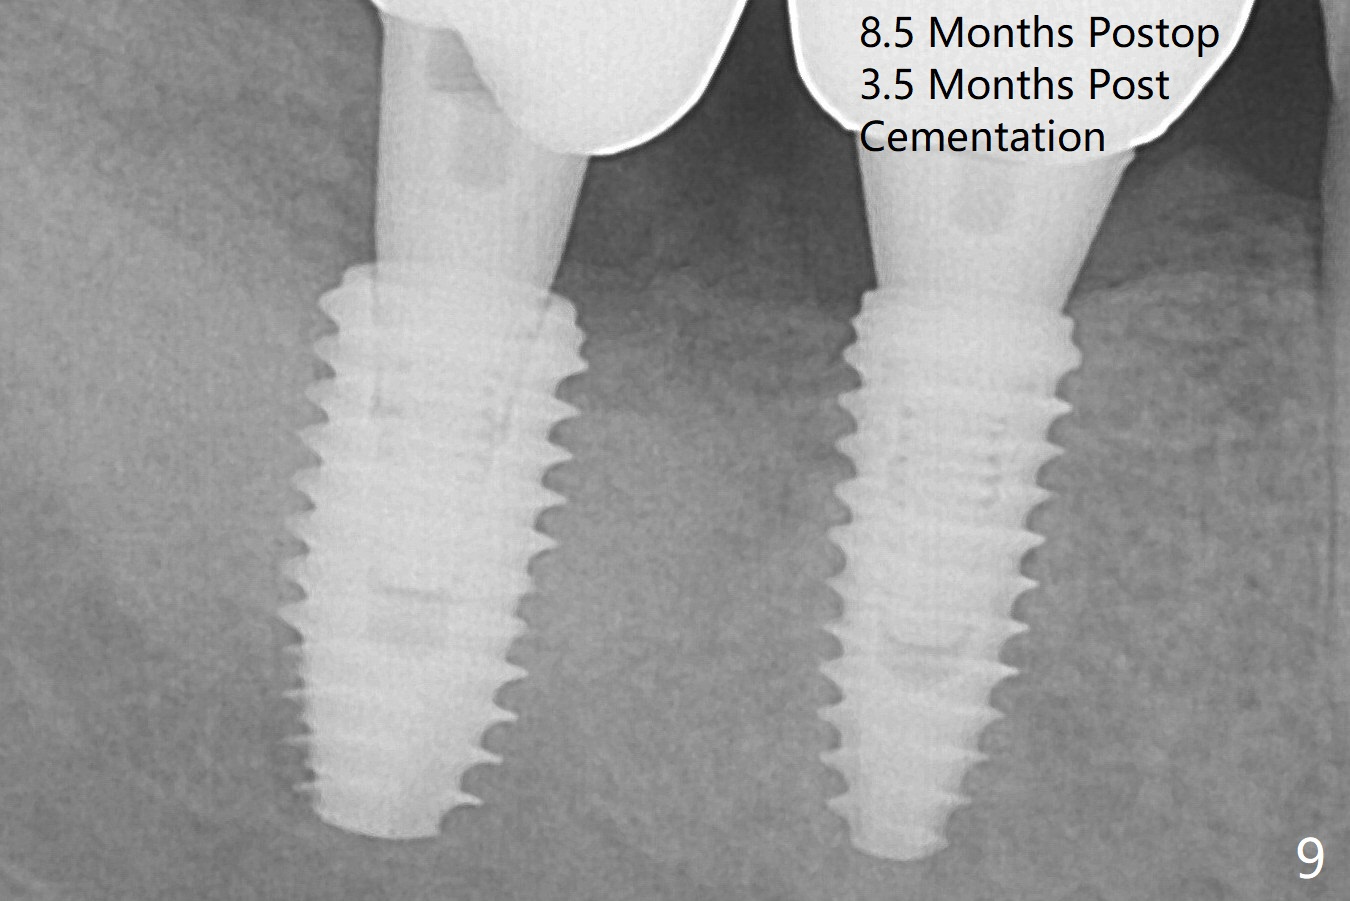

The loose implant is pushed distal (Fig.4 arrow) with placement of autogenous bone mesial (*). The stable implant at #30 (Fig.3) and its abutment (Fig.4) are used as a post to hold periodontal dressing, which covers the wound at #31 after placement of collagen plug and suturing. The bone graft seems to remain in place, while the implants remain parallel to each other 3 months postop (Fig.7). The implant is uncovered with placement of a 6.8x7 mm healing abutment 4 months postop. When a cementation abutment (4.5x5.5(4) mm) is placed, the buccal margin is much lower than the lingual. The patient enjoys mastication with the new implant crowns 3.5 months post cementation; the bone density around the implant at #31 increases (Fig.9).